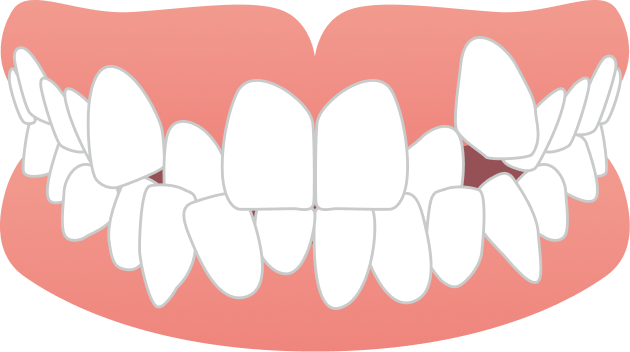

40代女性 前歯のガタガタが気になる

40代女性の患者さまで、前歯のガタつきを主訴にご相談に来院されました。マスクを外す機会が増えたことで歯並びが気になるようになり、また周囲で矯正治療をされた方がいらしたこともきっかけとなり、治療をご検討されたそうです。見た目が目立たず、できるだけ痛みの少ない方法で治療を進めたいというご希望をお持ちでした。

BEFORE